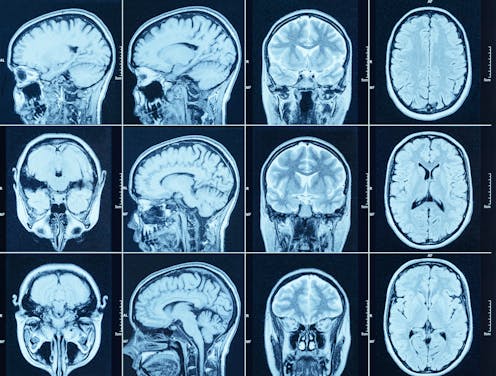

Meanwhile, it is possible to measure brain development with imaging technologies such as ultrasound, magnetic resonance imaging (MRI) and computerised tomography (CT). The development of these technologies has led to a wealth of research on how the brain changes, and each year, millions of clinical brain scans are performed worldwide. Despite this progress, there are few measures that are used to aid in monitoring brain development. Why?

In contrast to traditional growth charts, quantifying brain development and ageing comes with a host of technical obstacles. Simply put, there is no tape measure for the brain. This makes it difficult to standardise measures across different studies. The costs and complexity of acquiring brain scans mean the data available to generate reference charts for a single study is limited.

There is still much work to be done before these brain charts can be used as reference tools by healthcare professionals. The underlying dataset contains both ongoing studies, and those that were started as early as 1990 when MRI machines were in a select few places in the world. So the brain charts can constantly be updated, expanded and refined.

As larger datasets become more of the norm, we hope to continue to make our reference charts more inclusive and representative. As brain scanning becomes cheaper and increasingly accessible (even portable), we hope our brain charts will enable more quantitative standards and aid neuroscientific discoveries to parallel these exciting technological advances.